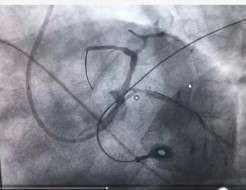

周亚峰副院长和张强主任接到消息,判断病人情况危重,急需手术治疗,立即至导管室进行各项术前准备,严阵以待。然而,刚抵达导管室门口沈先生就突发室速室颤、意识丧失、抽搐和呼吸停顿,随行医务人员立刻就地抢救,边进行心肺复苏边将沈先生转移至手术台上。手术过程中沈先生仍有室速室颤反复发作的情况,共进行8次紧急电除颤(见图1),术中导丝通过冠脉导管迅速送至冠脉血管,发现前降支近主干段完全闭塞(见图2),回旋支开口至近段狭窄50%,右冠开口狭窄约80%,周亚峰副院长以最快速度开通“罪犯血管”,于前降支近段植入支架一枚(见图34)。经过一个多小时的抢救和手术,患者胸痛症状明显减轻,手术取得圆满成功。

图1患者室速发作时的心电图